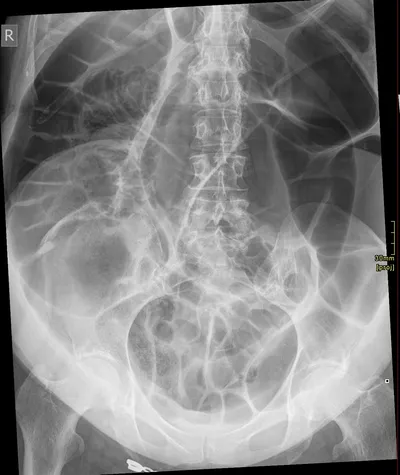

Left sided pubic ramal fractures

XRAYPelvisfracture

4/23/2026